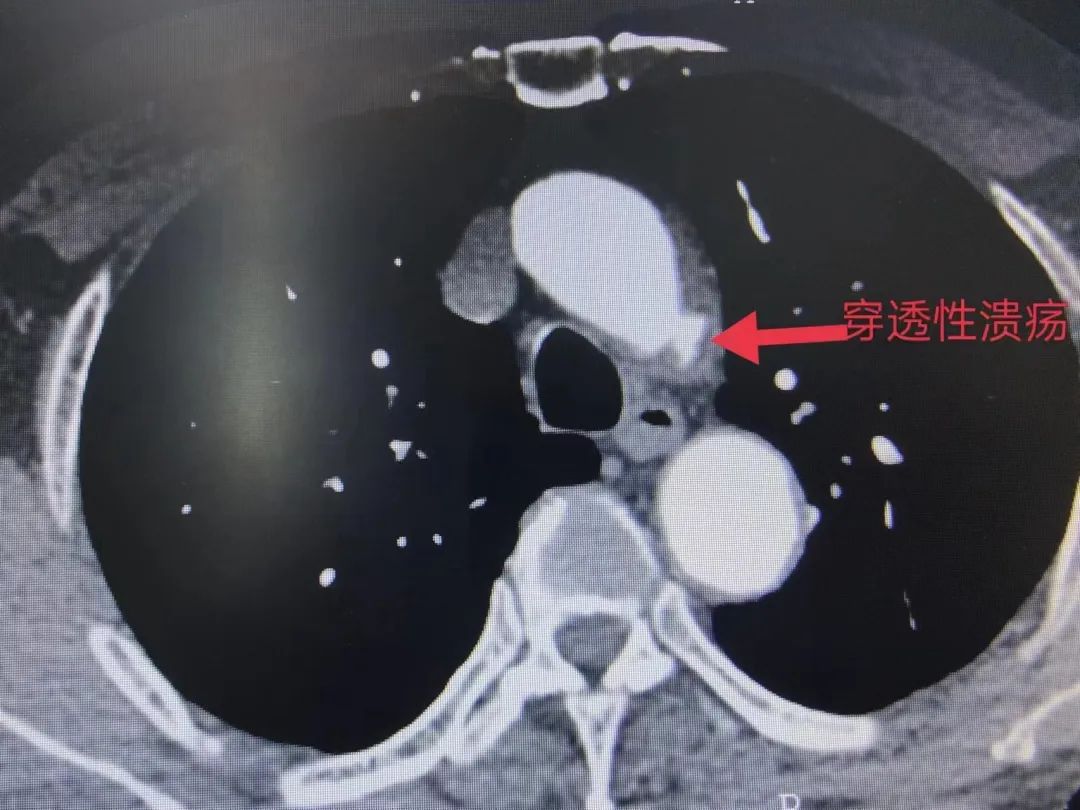

王老汉主动脉弓小弯侧主动脉上有一个穿透性溃疡,病情复杂。

刘伟超副主任医师解释说,穿透性溃疡就是“血管壁破了个洞”,单纯的覆膜支架不能有效地解决问题,需要行体外预开窗保留左锁骨下动脉。体外开窗就是在手术中把这个直径不到1厘米的血管对准支架上不到1厘米的开窗位置。体外预开窗技术是国内前沿技术,我科自2014年开展此项技术,目前已日臻成熟。